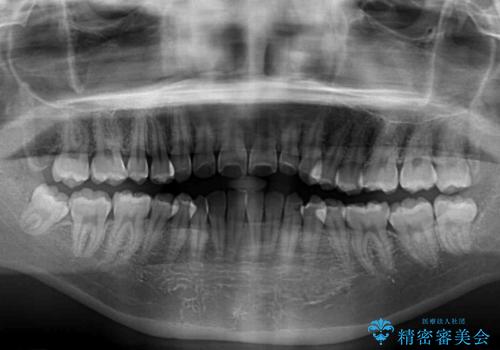

- 上下のデコボコと奥歯の咬みにくさを気にして来院された患者様です。

上顎骨の幅が下顎骨よりも小さく受け口傾向であったため、拡大装置により上顎骨の骨幅を広げて上下関係を改善し、その後インビザラインにて歯並びを整えることとしました。

下顎歯列は上顎歯列内に収まるように並んでいますが、上顎骨の幅が狭いと、下顎臼歯が全体的に舌側に傾斜した歯列となってしまいます。

舌側に傾斜した歯列は奥歯に力の負担がかかりやすく、歯磨きがしにくいなどの問題があるため、上顎骨拡大により舌側傾斜を改善することが可能となります。